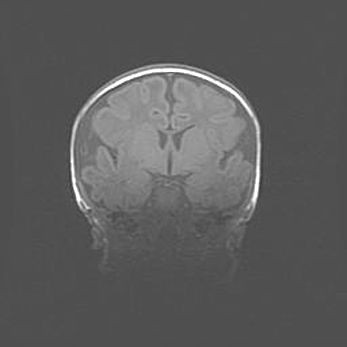

Наружная гидроцефалия с возможной атрофией височных областей.

Возраст: 28 дней

Вес: 3670 г

Пол: мужской

Окружность головы: 38 см

Срок гестации: 40 недель

Гидроцефалия головного мозга у новорожденных – это заболевание, которое характеризуется скоплением избыточного количества спинномозговой жидкости в желудочковой системе головного мозга в результате затруднения её перемещения от места выработки к месту поглощения в кровеносную систему или вследствие нарушения абсорбции. При открытой наружной форме гидроцефалии у новорожденных расширяются и переполняются субарахноидные пространства.

При нормотензивных  формах,  которые,  как  правило,  являются  следствием  перенесенных ишемических  повреждений  паренхимы  мозга,  возможно  сочетание микроцефалии  с нормотензивной гидроцефалией. В основе данных изменений лежит атрофия больших полушарий с преимущественной  локализацией  в  лобно-височных  областях.